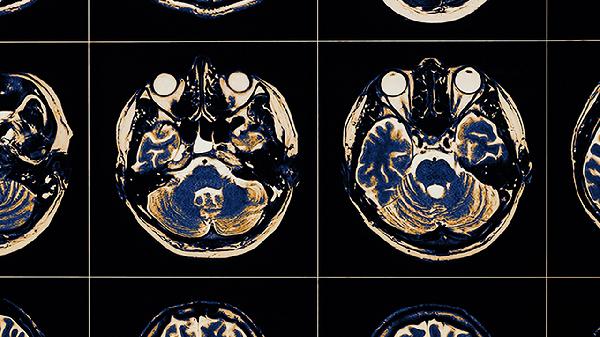

补充海马体功能可适量吃深海鱼、坚果、蓝莓、鸡蛋、菠菜等食物,也可遵医嘱服用奥拉西坦胶囊、吡拉西坦片、胞磷胆碱钠胶囊、银杏叶提取物片、盐酸多奈哌齐片等药物。海马体是大脑负责记忆和学习的关键区域,其健康与饮食营养密切相关。